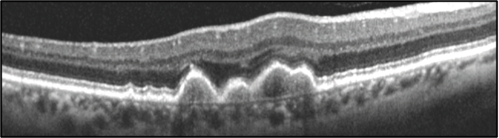

Figure 1. "Leptochoroid" refers to a thin choroid, as seen here. This is a 69-year-old male with early AMD.